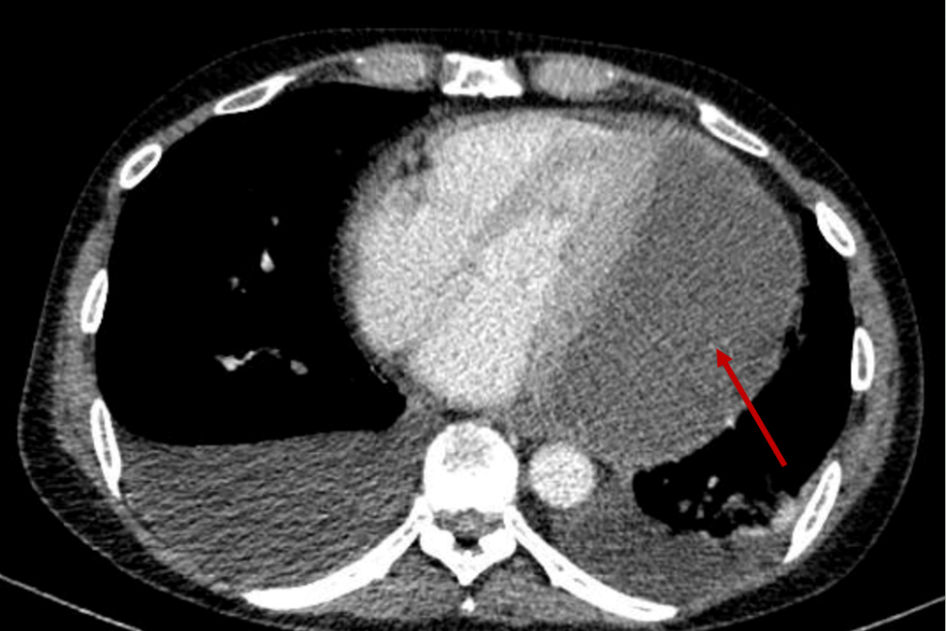

Nam bệnh nhân 3 lần thủng đường tiêu hóa trong 4 tháng

Bệnh viện Đa khoa Cẩm Phả hiện đang điều trị cho một nam bệnh nhân (57 tuổi) nhập viện trong tình trạng cực kỳ nguy kịch, gặp nhiều biến chứng phức tạp sau nhiều lần bị thủng đường tiêu hóa.